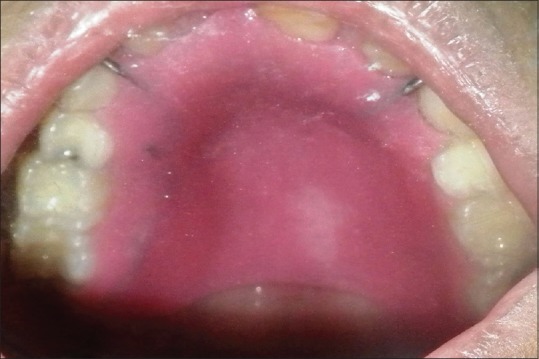

A 6-year-old boy, case of ALL, was referred for prosthetic rehabilitation of a palatal perforation following chemotherapy [Figure 1]. A detailed case history revealed that the patient was diagnosed with B-cell ALL at the age of 5 years and was on consolidation chemotherapy. Palatal biopsy showed hyperplastic ulcerated squamous epithelium admixed with scanty bony bits and necroinflammatory cells with underlying granulation tissue. Ulcer slough contained a few fungal hyphae suggestive of secondary colonization. Noncontrast computerized tomography scan revealed mucosal pansinusitis and rhinitis. Nasal secretion test for fungal identification and susceptibility testing showed the presence of Candida tropicalis. On oral examination, a 2 cm × 2 cm perforation was seen on the left side of the hard palate with slough. It was decided to make a palatal obturator to cover the palatal perforation. This defect in the palate led to difficulty in eating, swallowing, and nasal regurgitation. Speech too was hypernasal and not intelligible. It was decided to cover the palatal perforation by fabrication of a palatal obturator.

| Figure 1:Intraoral view showing the palatal perforation